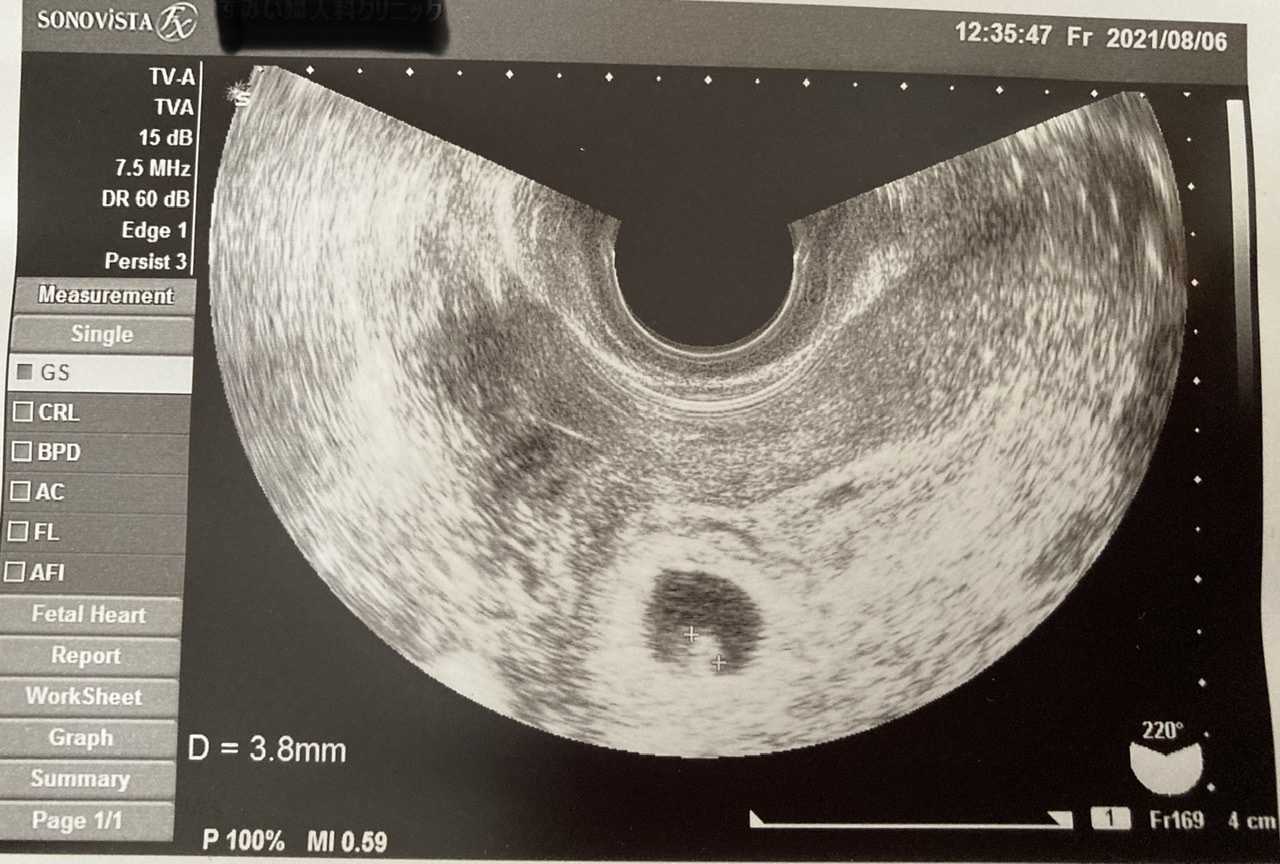

妊娠2ヶ月 (妊娠6週目):心拍確認! まだ微妙な出血は続いていますが、とりあえず検診に。 なんとなく体は少し軽くなった感じ。 駅くらいまでなら歩けそう。 ってことで、普通に電車に乗って検診へ。 子宮口にあるポリープからの出血はなさそう妊娠6週ころの超音波写真 心拍が確認できることもあります 小さな豆粒の赤ちゃん(胎芽)が細長く成長してきます。 心拍を確認できることもありますが、まだ微弱です。 超音波写真では豆粒ですが、実際は目や口、手、足のもとがつくられています 6週だと心拍確認できないこともありますよ。 6週目で胎嚢確認、心拍ナシ。 7週目も同じだった時、医師から流産の可能性が少なからずあると

妊婦 7 週目で心拍が確認できましたが、 122 回 / 分と書かれてました。 7 週目だと最低でも 140 回 / 分だと聞いたのですが、、、 心臓が止まり、流産の可能性はありますか? Q. 4 現在、妊娠 9 週目ですが、先日の診察で胎児の心拍数が高いと言われ心配し妊娠週 6w1d 排卵日が特定できているので、確実に6w1dのエコーです (^^)元気な心拍と2mmの赤ちゃんが確認できました! 2人目の妊娠なので、まだ1歳10ヶ月の長男を抱っこしたり追いかけ回したりでゆっくりできないので、赤ちゃんが心配ですが生命力を信じて 妊娠6週で胎嚢が見えない、7週でも心拍が確認できなかった話 01 検査薬陽性 02 産婦人科受診 04 無事胎嚢確認 05 妊娠9週目の検診でやっと心拍確認

心拍確認はいつ?何週目でできた?体外受精の場合 結果!無事、心拍確認できました(tt) 心拍確認できたのは、 7週目5日目 でした。 早いと6週目くらいからできるみたいですが、私はhcgの上昇が遅かったこともあり7週5日目でもギリギリくらいだったと思います。6w入って心拍確認できませんでした。先生には、6週入ったら100%心拍確認 6w入って心拍確認できませんでした。 先生には、6週入ったら100%心拍確認できる。 次は2週間後に来て、その時どちらか確定すると言われ 不安でいっぱいです。 6週目頃~8週目頃 に確認できる と言われています。 いろいろなサイトをみていると 6週目頃 に心拍を確認できた人が 多くいるように思えますが 排卵がずれていたりすると それ以上かかる人ももちろんいらっしゃいます。 こちらの動画が 心拍確認 が